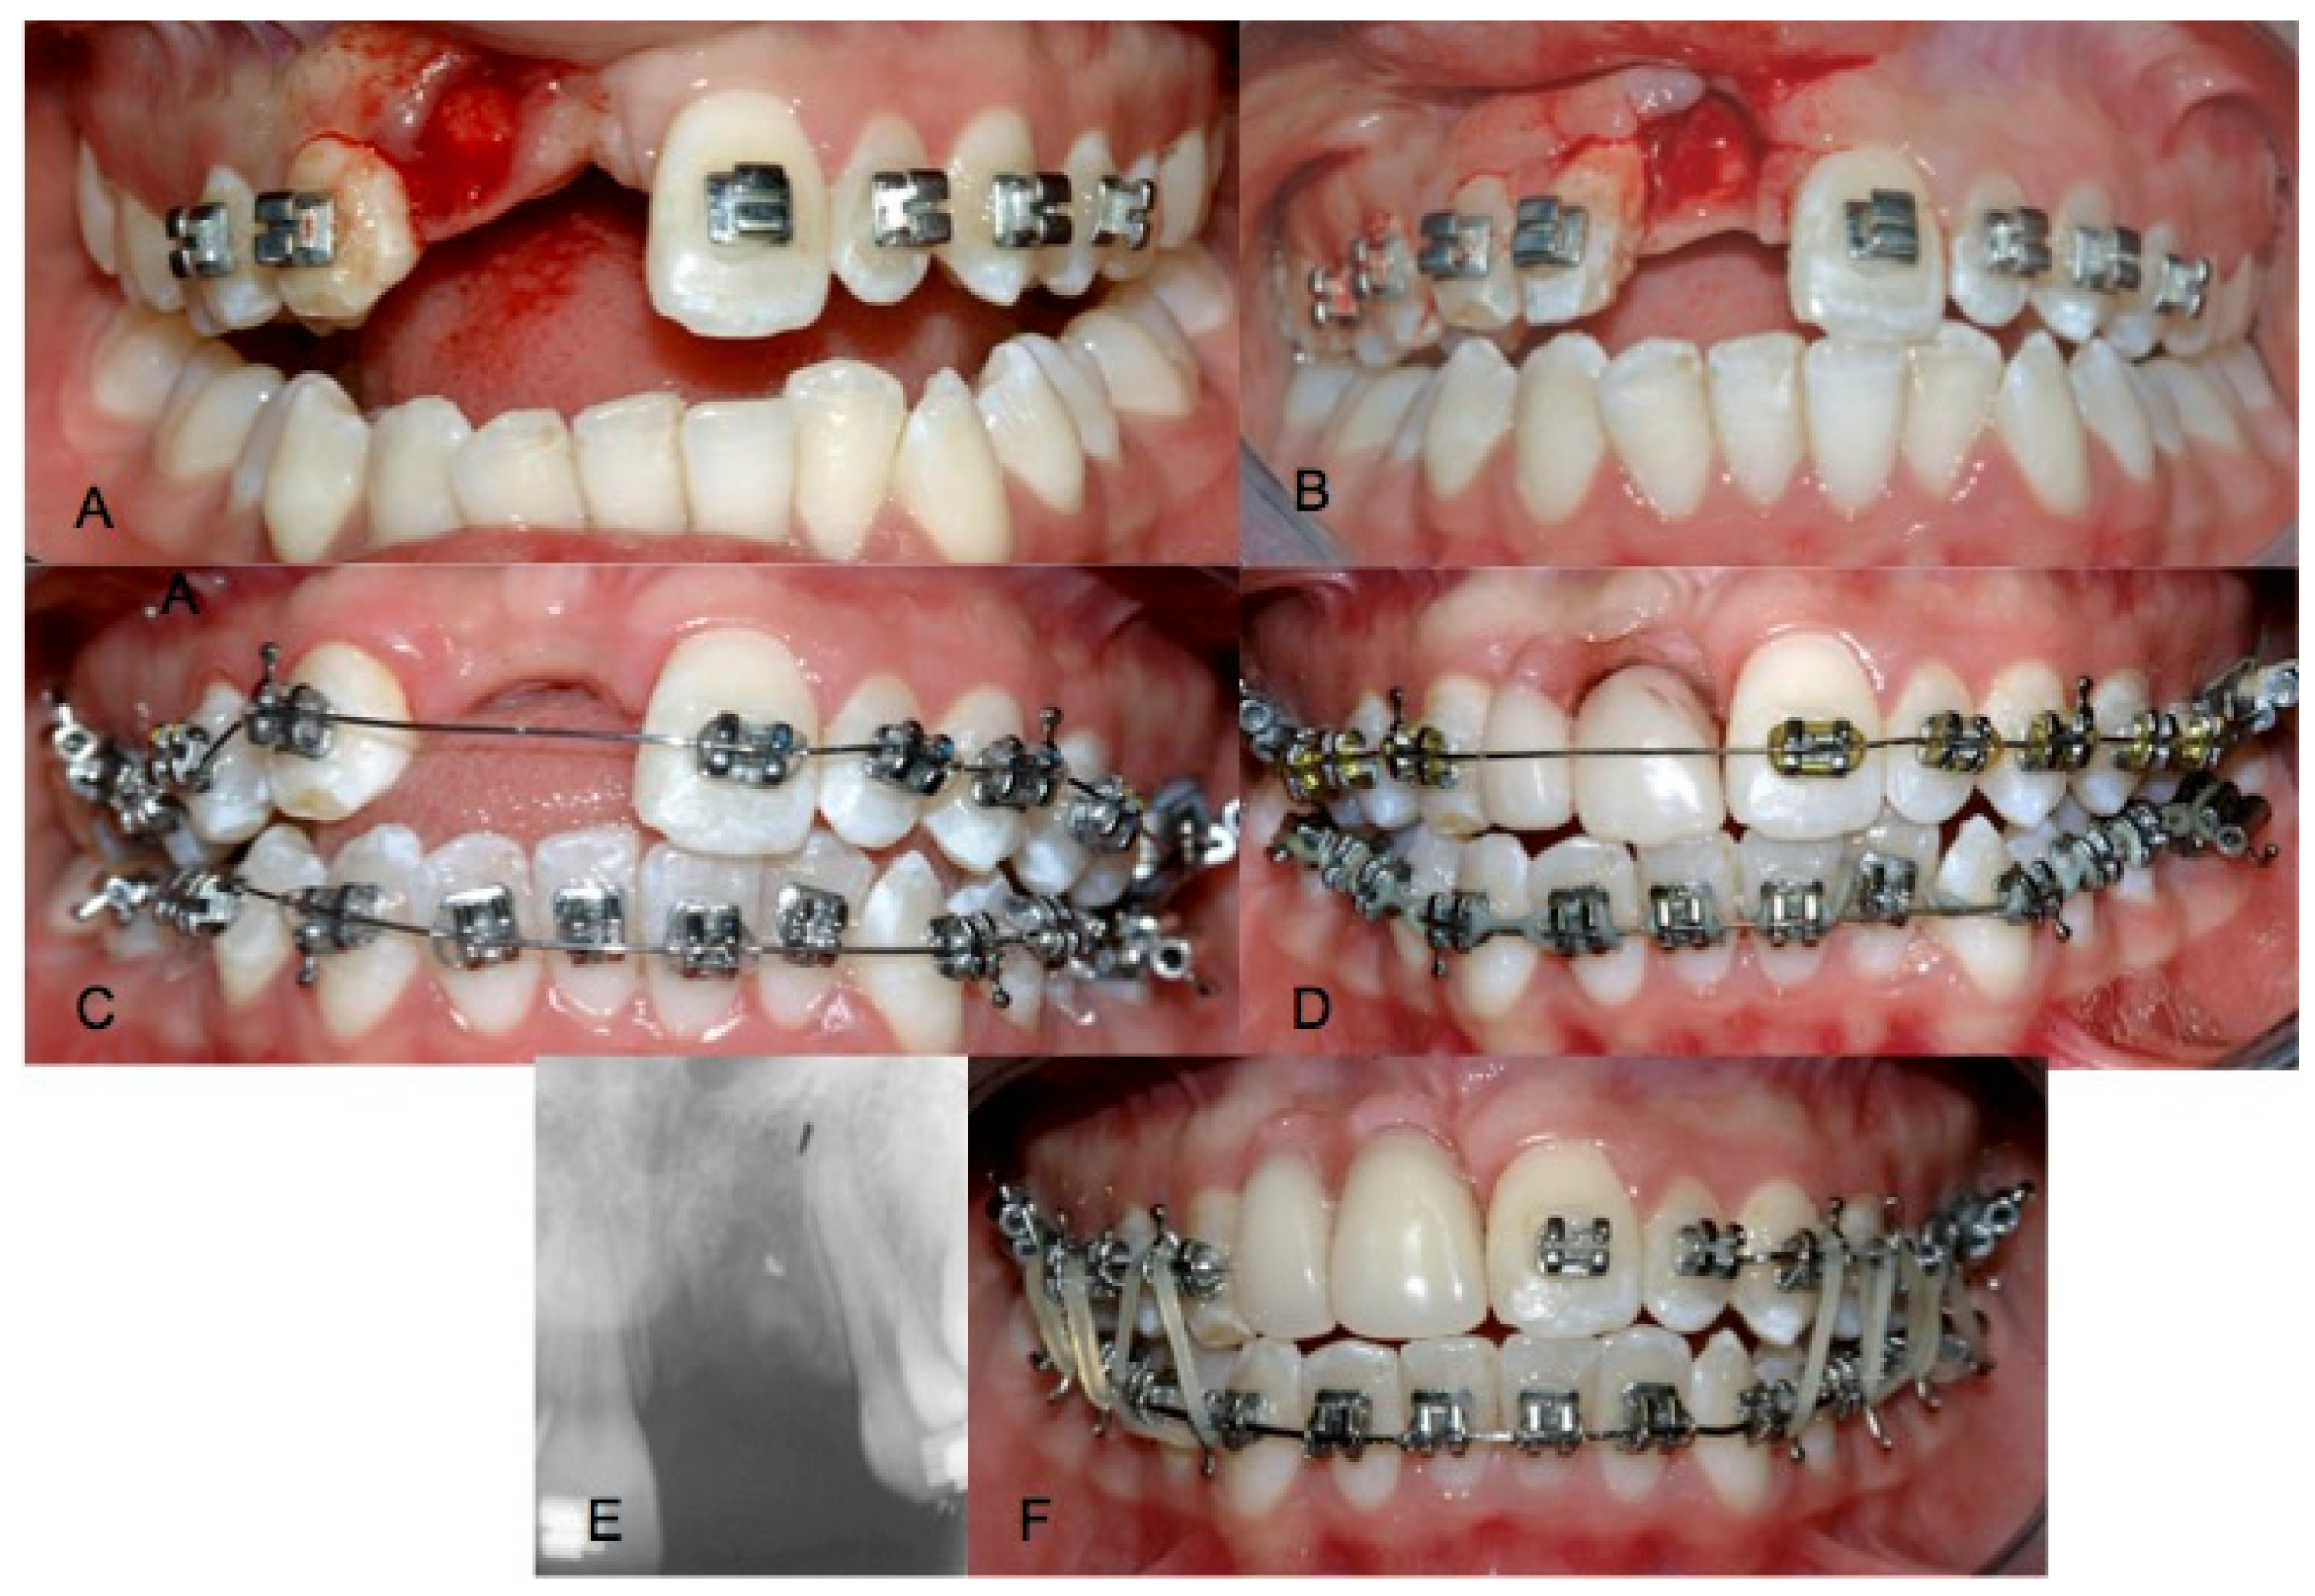

2. Case Report